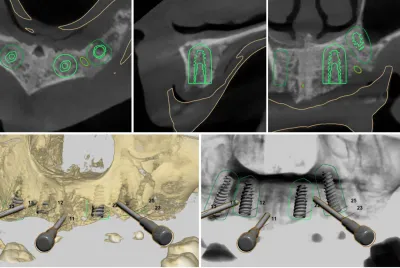

spécialiste implantologie dentaire Marseille

L'implantologie dentaire a connu un développement technique important ces dernières années et est devenue une discipline indépendante de la dentisterie .Les cas complexes doivent être abordés avec un spécialiste en Implantologie dentaire.